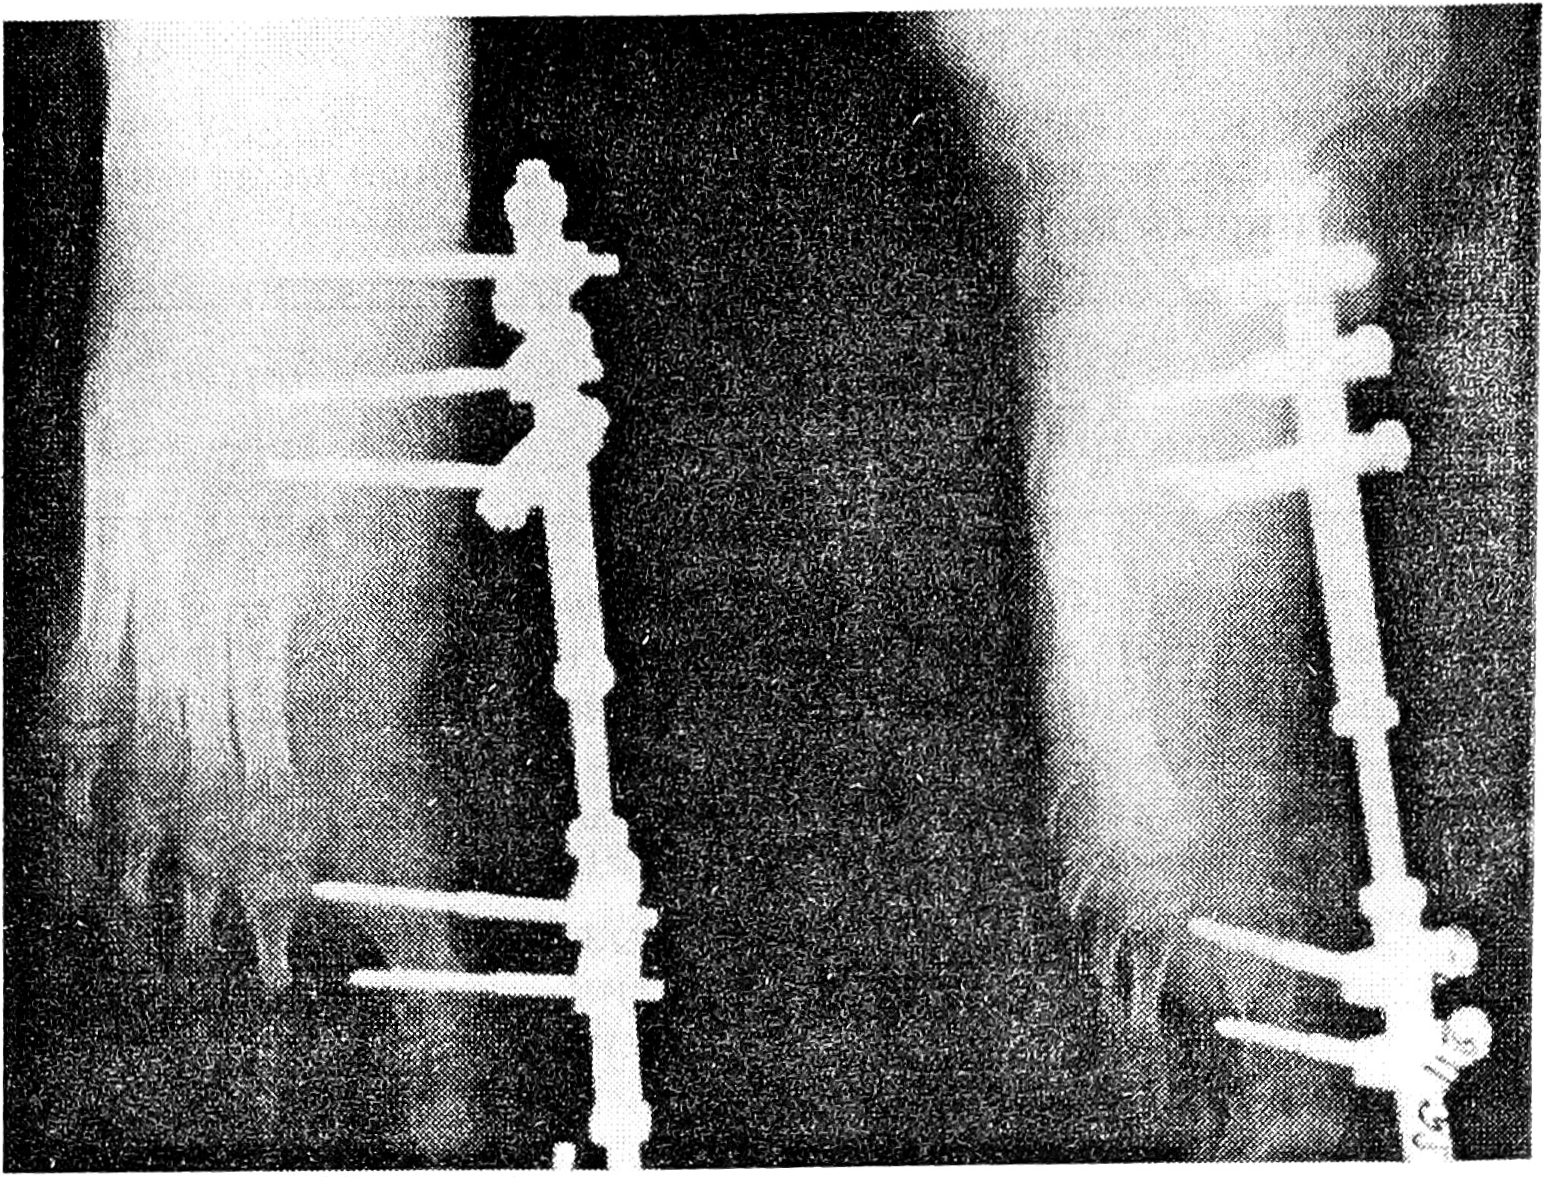

Больная К., 13 лет, поступила в ЦИТО по поводу тотального дефекта I плюсневой кости правой стопы вследствие посттравматического остеомиелита и неоднократных секвестрэктомий, с жалобами на затрудненную ходьбу и нарастающую деформацию I пальца (рис. 1). Первым этапом на I луч стопы был наложен стержневой компрессионно-дистракционный аппарат, с помощью которого создан диастаз на длину пястной кости между клиновидной костью и основной фалангой пальца (рис. 2). После этого 19.09.95 под общим обезболиванием двумя бригадами хирургов произведены замещение дефекта плюсневой кости свободным васкуляризированным малоберцовым трансплантатом, эндопротезирование плюснефалангового сустава силиконовым эндопротезом, пластика дефекта кожи полнослойным кожным трансплантатом (рис. 3). Одна бригада хирургов иссекла рубцы по внутренней поверхности стопы, выделила для наложения микрососудистых анастомозов заднюю большеберцовую артерию и сопровождающие ее вены, подготовила ложе для костного трансплантата. Вторая бригада в это время производила забор малоберцового костного трансплантата длиной 9,5 см с питающей его артерией и венами, мышечной муфтой толщиной 0,8 см. Затем костный трансплантат был адаптирован на стопе и фиксирован к соседним костям спицами Киршнера (рис. 4). Перед выполнением остеосинтеза на дистальный конец трансплантата был «надет» соответствующего размера силиконовый эндопротез, предназначенный для замещения головки плюсневой кости. Наложены микроанастомозы между артерией костного трансплантата и задней большеберцовой артерией и сопровождающими их венами. После снятия сосудистых клипсов отмечено обильное капиллярное кровотечение из мышечной муфты, свидетельствующее о хорошей проходимости сосудистых микроанастомозов и кровообращении в трансплантате. (Последнее было многократно подтверждено в разные сроки послеоперационного периода допплерографически.) На рану наложены послойные швы. Оставшийся кожный дефект размером 1,2 × 4 см закрыт полнослойным кожным аутотрансплантатом. Наложены асептическая повязка и задняя гипсовая лонгета с фиксацией стопы в положении, исключающем малейшее натяжение микрососудистых анастомозов.

Рис. 2. Рентгенограммы правой стопы со стержневым аппаратом перед операцией.

Рис. 4. Рентгенограммы стопы через 3 нед после замещения дефекта плюсневой кости васкуляризированным малоберцовым трансплантатом.